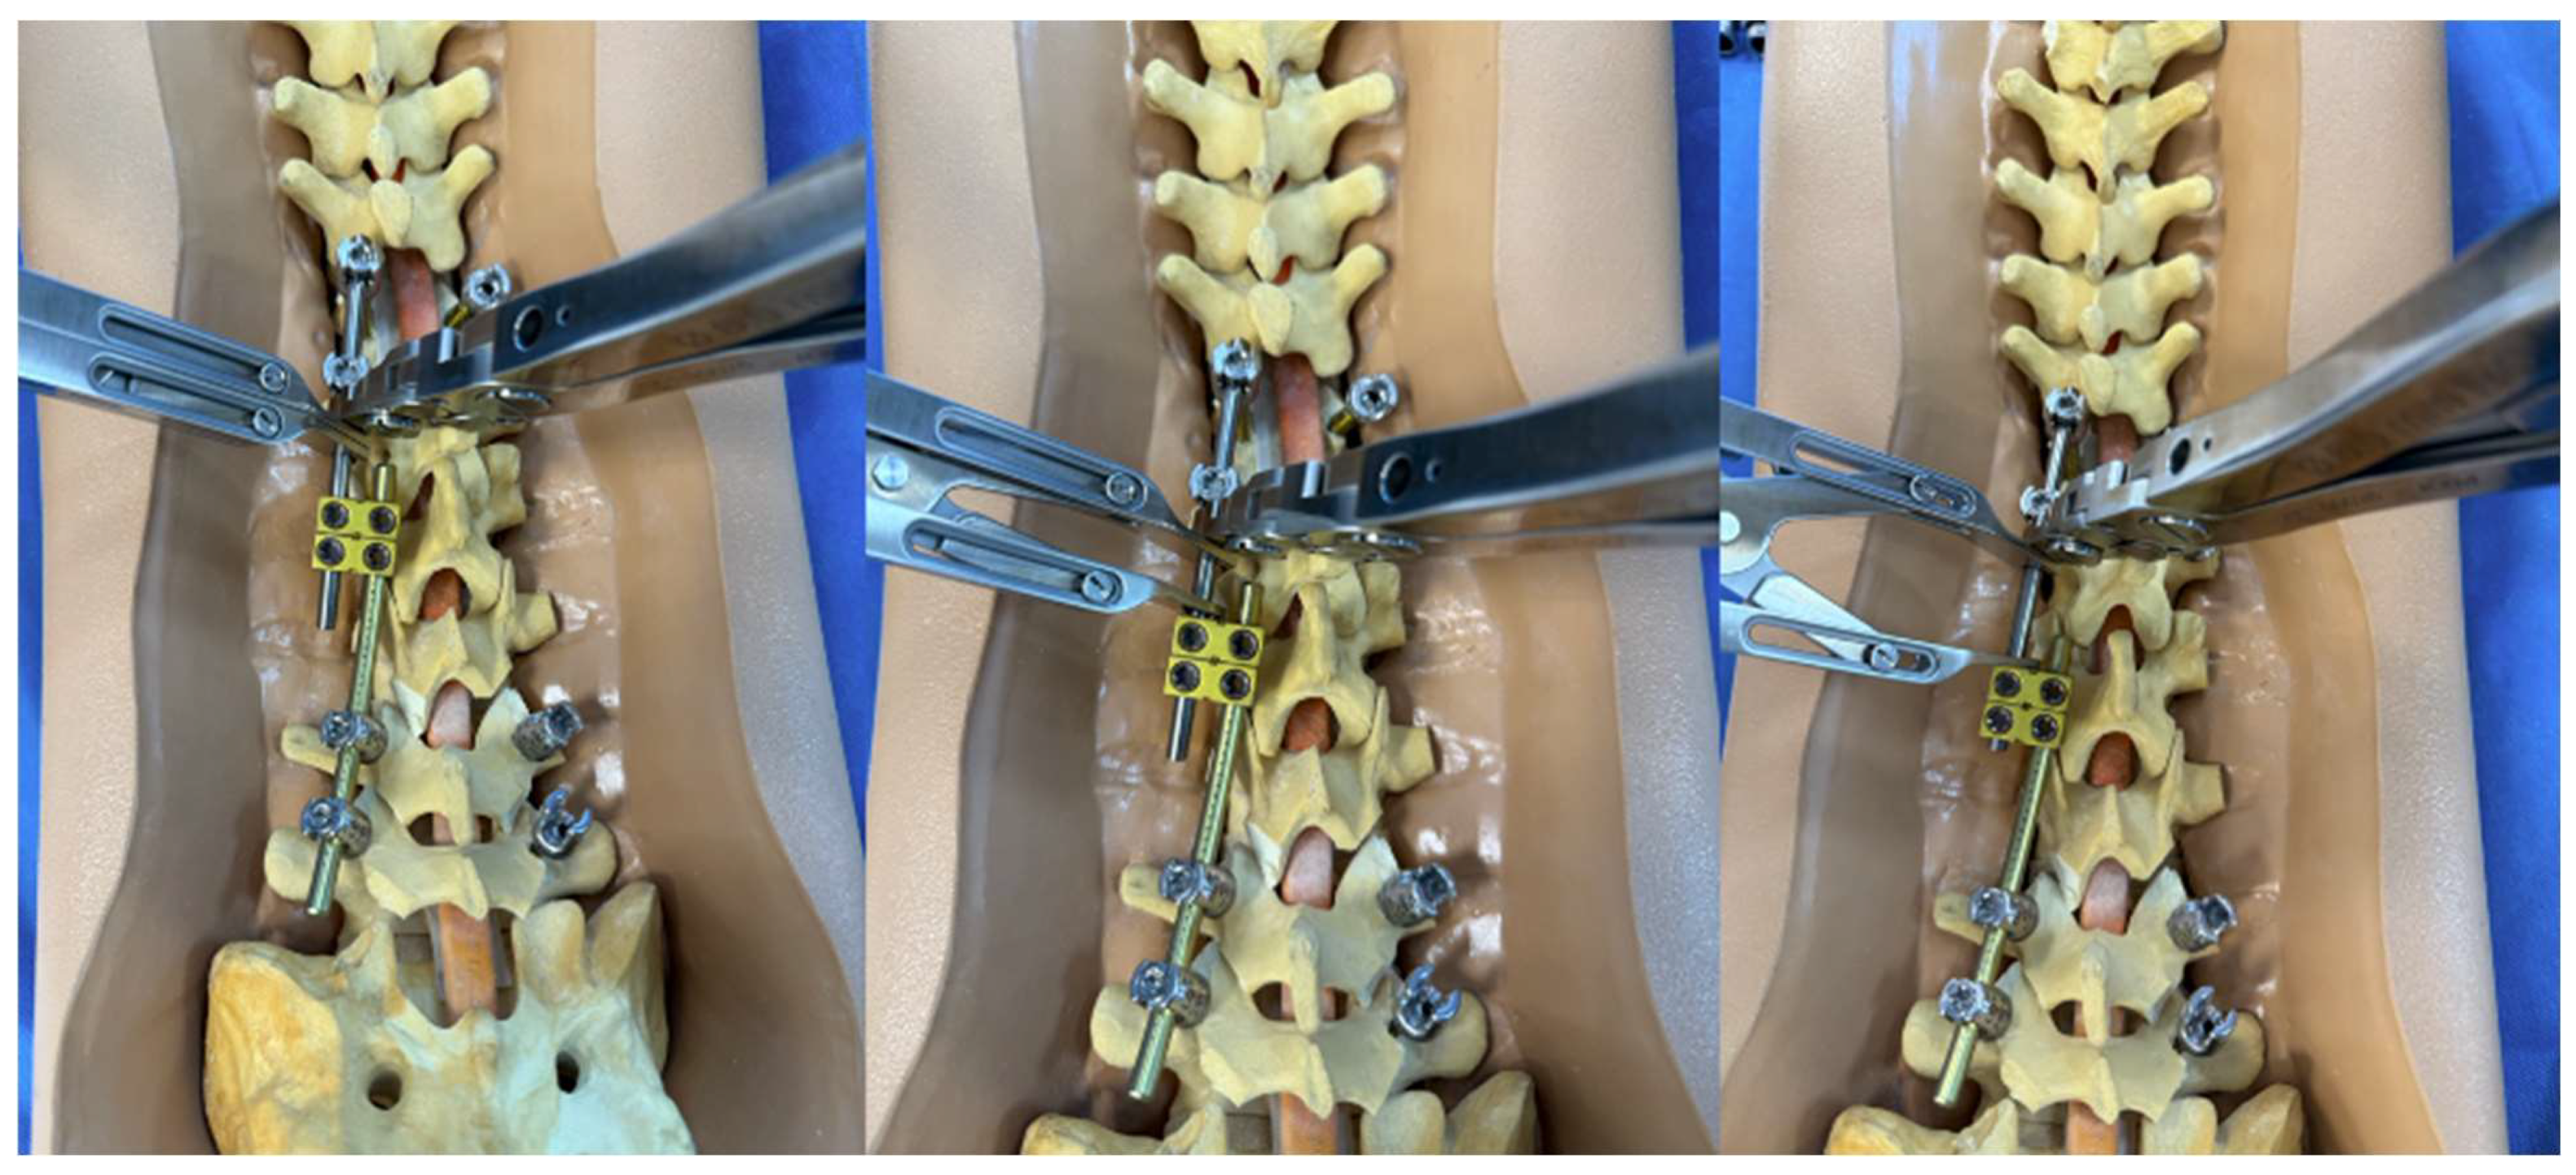

Pedicle subtraction osteotomies (PSOs) represent Schwab 3 and 4 osteotomies and are powerful techniques for correcting both sagittal and coronal fixed, spinal deformities [7]. The PSO is the first three-column osteotomy described in this technique paper. The construct-to-construct internal compression technique represents one method of closing this osteotomy. We recommend having several anchor points above and below the PSO level (three levels of fixation are preferred if possible). In the case of lumbar PSOs, a contoured rod is fixed to the distal anchor points and cantilevered over the osteotomy to connect into one or two domino connector(s) to form the construct-to-construct configuration [8]. A rod gripper attaches to this distal contoured rod, and a compressor is placed between the domino connector(s) and the rod gripper (Figure 7). Gradual compression is applied in a controlled, “click-by-click” manner before the set caps are tightened to hold the correction. This process is repeated on the contralateral side to finish closing down the osteotomy.

Figure 7. Step-by-step schematic of the construct-to-construct internal compression technique for closure of PSO. The green caps represent loose set caps. Red caps represent tight set caps (A). Intraoperative image adapted from Bourghli et al. showing a construct-to-construct internal compression technique to close a PSO site (B).